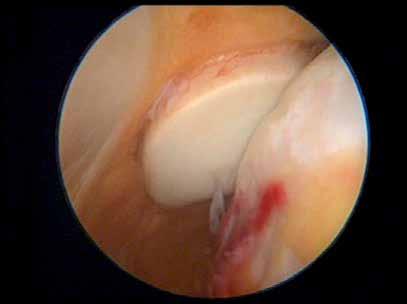

Arthroscopic views of maltracking patella as the knee is flexed (Siddiqui 2013).

Right patella and portion of the femoral condyle showing shiny areas of eburnation.

Right patella and portion of the femoral condyle with cross-lighting to show cog and wheel grooves in areas of eburnation.

Rogers 1993 looked at the ridges and grooves of eburnated bone on the two articulating surfaces of the bone which fitted together like cog-wheels,

see Figures on page 17, and again in (2004) he examined the presence of eburnation and osteophytes and their strong association.